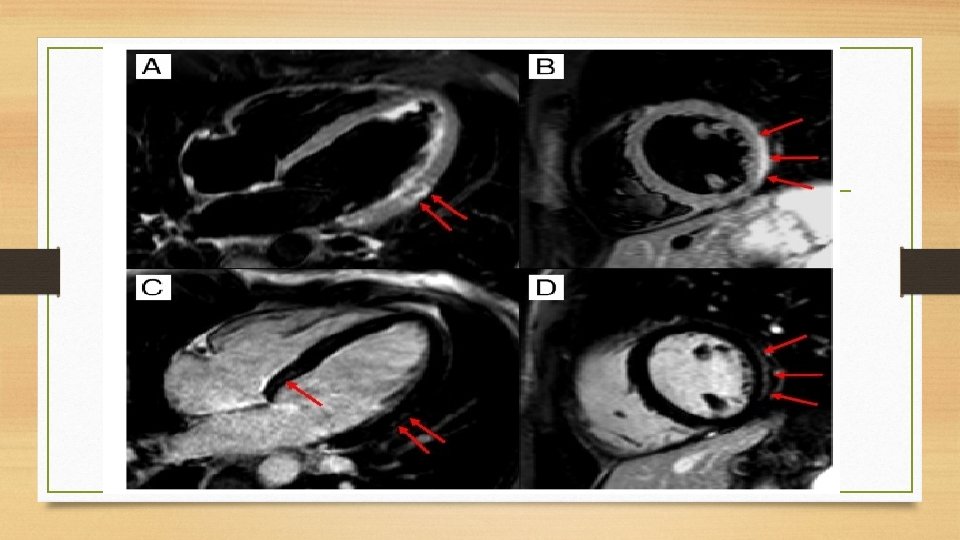

Blood • Cardiac Troponins-Acute or fulminant DCM with heart failure. • Sub acute or chronic myocarditis biomarkers are usually normal. Cardiac Magnetic Resonance • CE-CMR----detect areas of myocardial damage in patients with acute myocarditis. • c. MRI sensitivity and specificity are as high as 100% and 90%.

• T 2 -weighted CMR -oedema or water. • T 1 -weighted sequences -inflammation or fibrosis. • LGE------CS ----multiple, patchy mid myocardial lesions in a non coronary ------septal and RV involvement. • Acute DCM, CMR -myocarditis predict a greater likelihood of recovery, defined as a left ventricular ejection fraction (LVEF) >55% after 24 months

q Regional or global T 2 -weighted “oedema-sensitive” sequences also had a significant improvement in LVEF at 12 -month follow-up(Vermes et al- Eur Heart J Cardio vasc Imaging 2014). • LGE -3. 7%/year risk of a composite of cardiovascular adverse events. q LGE predicted a composite endpoint of cardiac death, heart failure hospitalization, ventricular tachycardia, and sudden death( Schumm J et al-J Cardiovas Magn Reson 2014. )

• Rim-like pattern --- septal wall or a sub epicardial distribution ----free LV lateral wall - PVB 19. • PVB 19 ---- CE -lateral wall • HHV 6 -----CE -mid wall ----inter ventricular septum. • CE- CMR : Guidance for EMB sampling when necessary. • Lacks the ability to determine the magnitude of inflammation. • Acute not in chronic myocarditis. • c MRI is a reliable method of detecting myocardial fibrosis in DCM